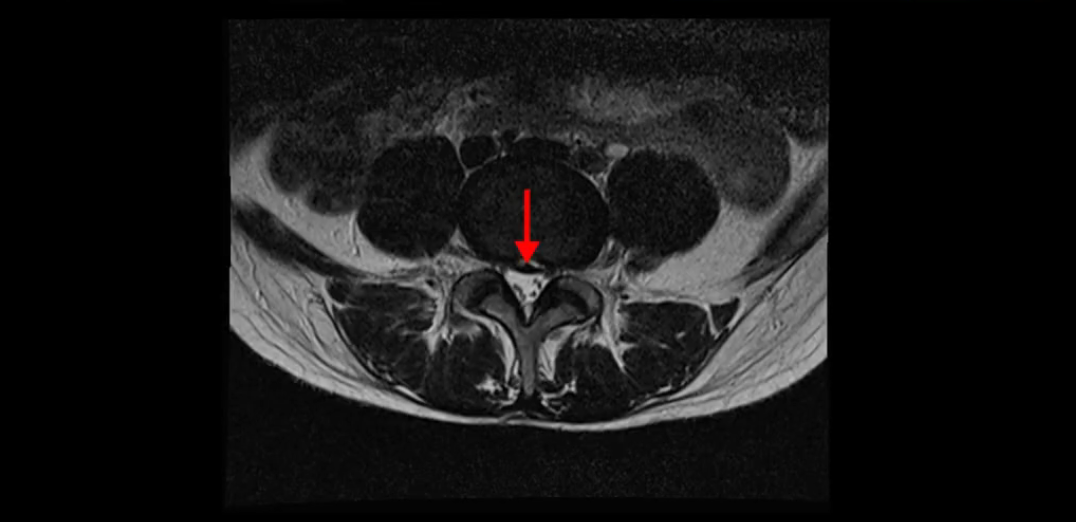

이분 MRI를 보시면 두 마디의 퇴행성디스크가 있습니다. 그리고 디스크가 조금씩 밀려 나와 있고요. 그런데 디스크 탈출 정도는 두 마디 다 심하지 않습니다. 4번 5번에는 디스크 탈출이 약간 있고,

척추관협착도 약간 진행이 되고 있고요.

5번 1번은 디스크 탈출이 가운데 쪽으로 살짝 있습니다.

중요한 것은 이 정도 경미한 탈출과 협착으로는 양쪽 다리가 저리고 아플 수가 없습니다.

이분 MRI를 보시면 퇴행성디스크가 있고 약간의 협착이 있지만 이 정도의 퇴행성디스크와 협착으로는 신경이 눌려서 양쪽 다리가 저리고 아픈 증상이 나올 수가 없습니다. 그래서 MRI와 이 환자분의 다리 증상이 매치가 안 된다고 하는 의사들이 많은 겁니다.